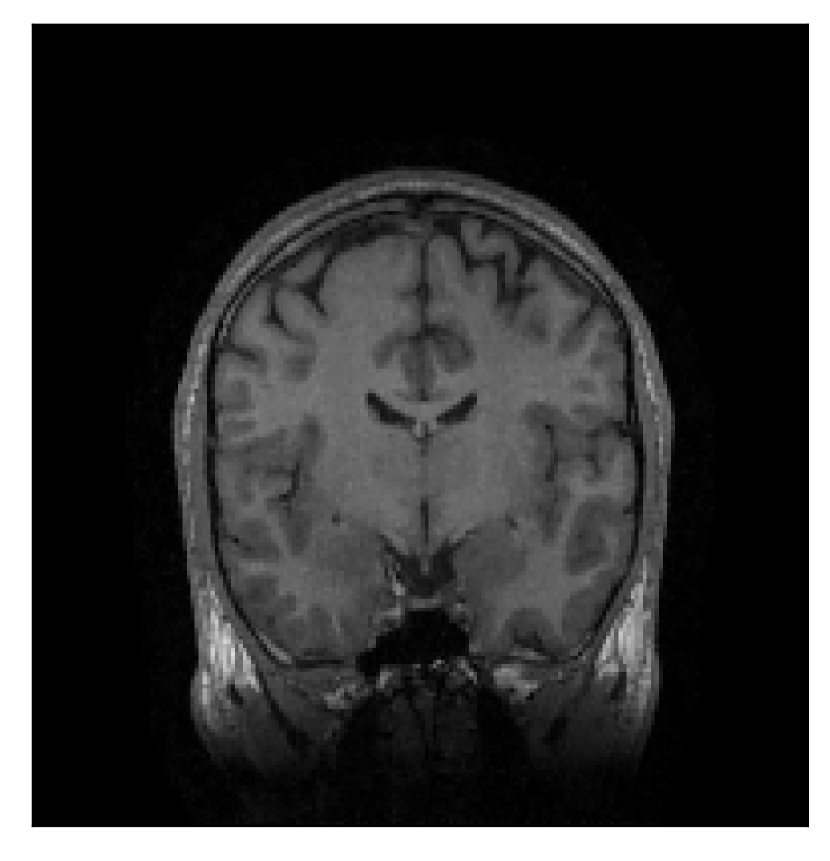

4.1 Experiment 1: robustness test

We gather the results for the robustness test described in Section 3.1 (volunteer 1) in Figures 2, 4, and 6 for motion corruption mechanisms associated to one, two, and five changes of position, respectively. Furthermore, we juxtapose the corrected images with varying degrees of corruption in Figure 8. We observe that the proposed method consistently ameliorates the corrupted scan. The quality indexes based on PSNR and SSIM show only a modest decrease in correction quality as a function of motion complexity (Figure 8).

| Section 3.1, Figure 2 | Sagittal | 23.94 | 27.95 | 0.7068 | 0.7936 |

| Coronal | 26.66 | 29.82 | 0.7653 | 0.8332 | |

| Axial | 25.40 | 30.16 | 0.7616 | 0.8490 | |

| Section 3.1, Figure 2 | T2-FLAIR | Completely corrected | Some blurring | No additional artifacts | Good grey white matter differentiation |